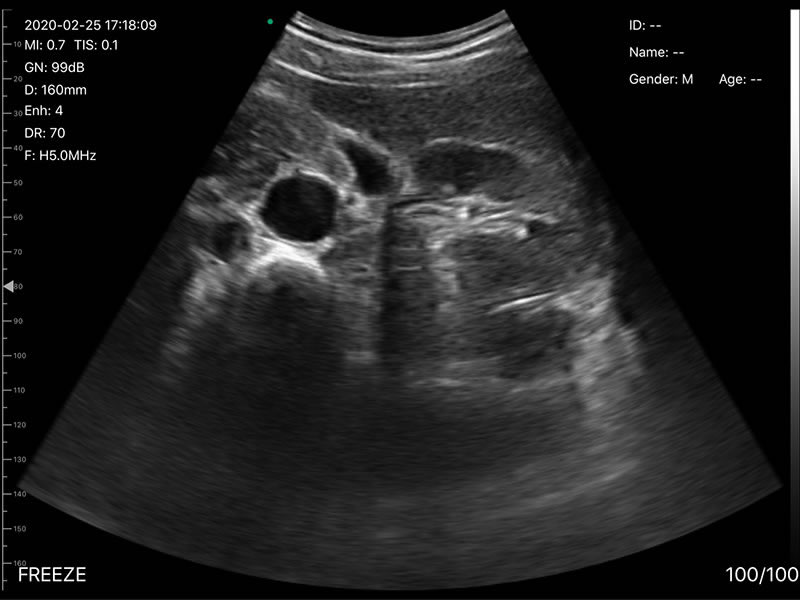

• Frequency: R60 Convex/Phasedarray probe 3.2MHz/5MHz,

• Display Depth: Convex 90/160/220/305mm, Linear 20/40/60/80mm

• Scan angle and width: convex 60°, Phasedarray 80°, linear 40mm